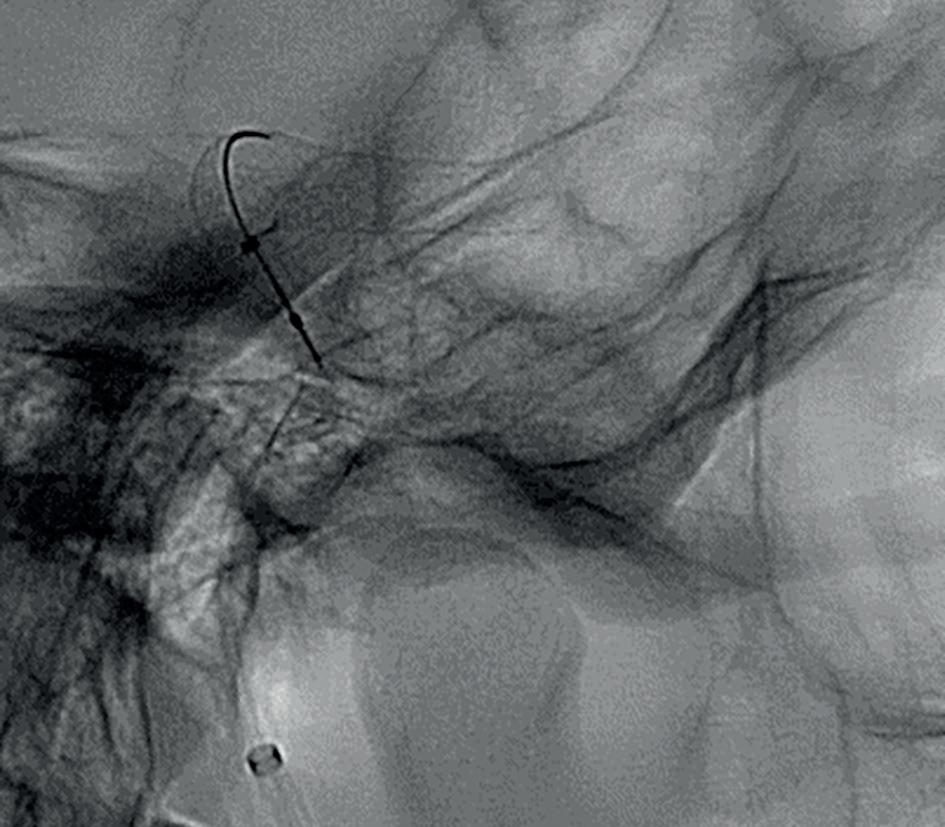

Bi-lobe ACA aneurysm treated with Target Detachable Coils